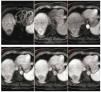

En agosto 2011, se realiza quimioembolización presentando respuesta parcial en el estudio de seguimiento a 3 meses. Se realizó QEIA nuevamente en diciembre 2011 (fig. 2). En seguimiento, se observa zona de captación en la periferia del tumor, en territorio subdiafragmático (fig. 3); en marzo del 2012 se decide realizar nueva QEIA. Por la localización de la zona con actividad, se realiza angiografía selectiva de probables ramas accesorias. En angiografía previa a la embolización, se identifica irrigación de la zona de actividad por parte de la arteria frénica derecha (fig. 4). Se realiza embolización blanda y ablación por radiofrecuencia (ARF). Última resonancia magnética dinámica de abril 2013, sin evidencia de activad tumoral (fig. 5).

Figura 3. RM de control. Se observa una zona de actividad periférica en segmento VII, que muestra restricción de la difusión (flecha) y realce arterial y lavado (cabeza de flechas) durante la fase dinámica. La zona hipodensa (*) corresponde a la zona de necrosis posterior a la QEIA.

Figura 5. RM de control, donde se muestra difusión y fase contrastada dinámica. No hay evidencia de realce que sugiera actividad tumoral.